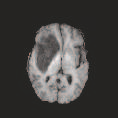

Multi-modal medical image completion has been extensively applied to alleviate the missing modality issue in a wealth of multi-modal diagnostic tasks. However, for most existing synthesis methods, their inferences of missing modalities can collapse into a deterministic mapping from the available ones, ignoring the uncertainties inherent in the cross-modal relationships. Here, we propose the Unified Multi-Modal Conditional Score-based Generative Model (UMM-CSGM) to take advantage of Score-based Generative Model (SGM) in modeling and stochastically sampling a target probability distribution, and further extend SGM to cross-modal conditional synthesis for various missing-modality configurations in a unified framework. Specifically, UMM-CSGM employs a novel multi-in multi-out Conditional Score Network (mm-CSN) to learn a comprehensive set of cross-modal conditional distributions via conditional diffusion and reverse generation in the complete modality space. In this way, the generation process can be accurately conditioned by all available information, and can fit all possible configurations of missing modalities in a single network. Experiments on BraTS19 dataset show that the UMM-CSGM can more reliably synthesize the heterogeneous enhancement and irregular area in tumor-induced lesions for any missing modalities.